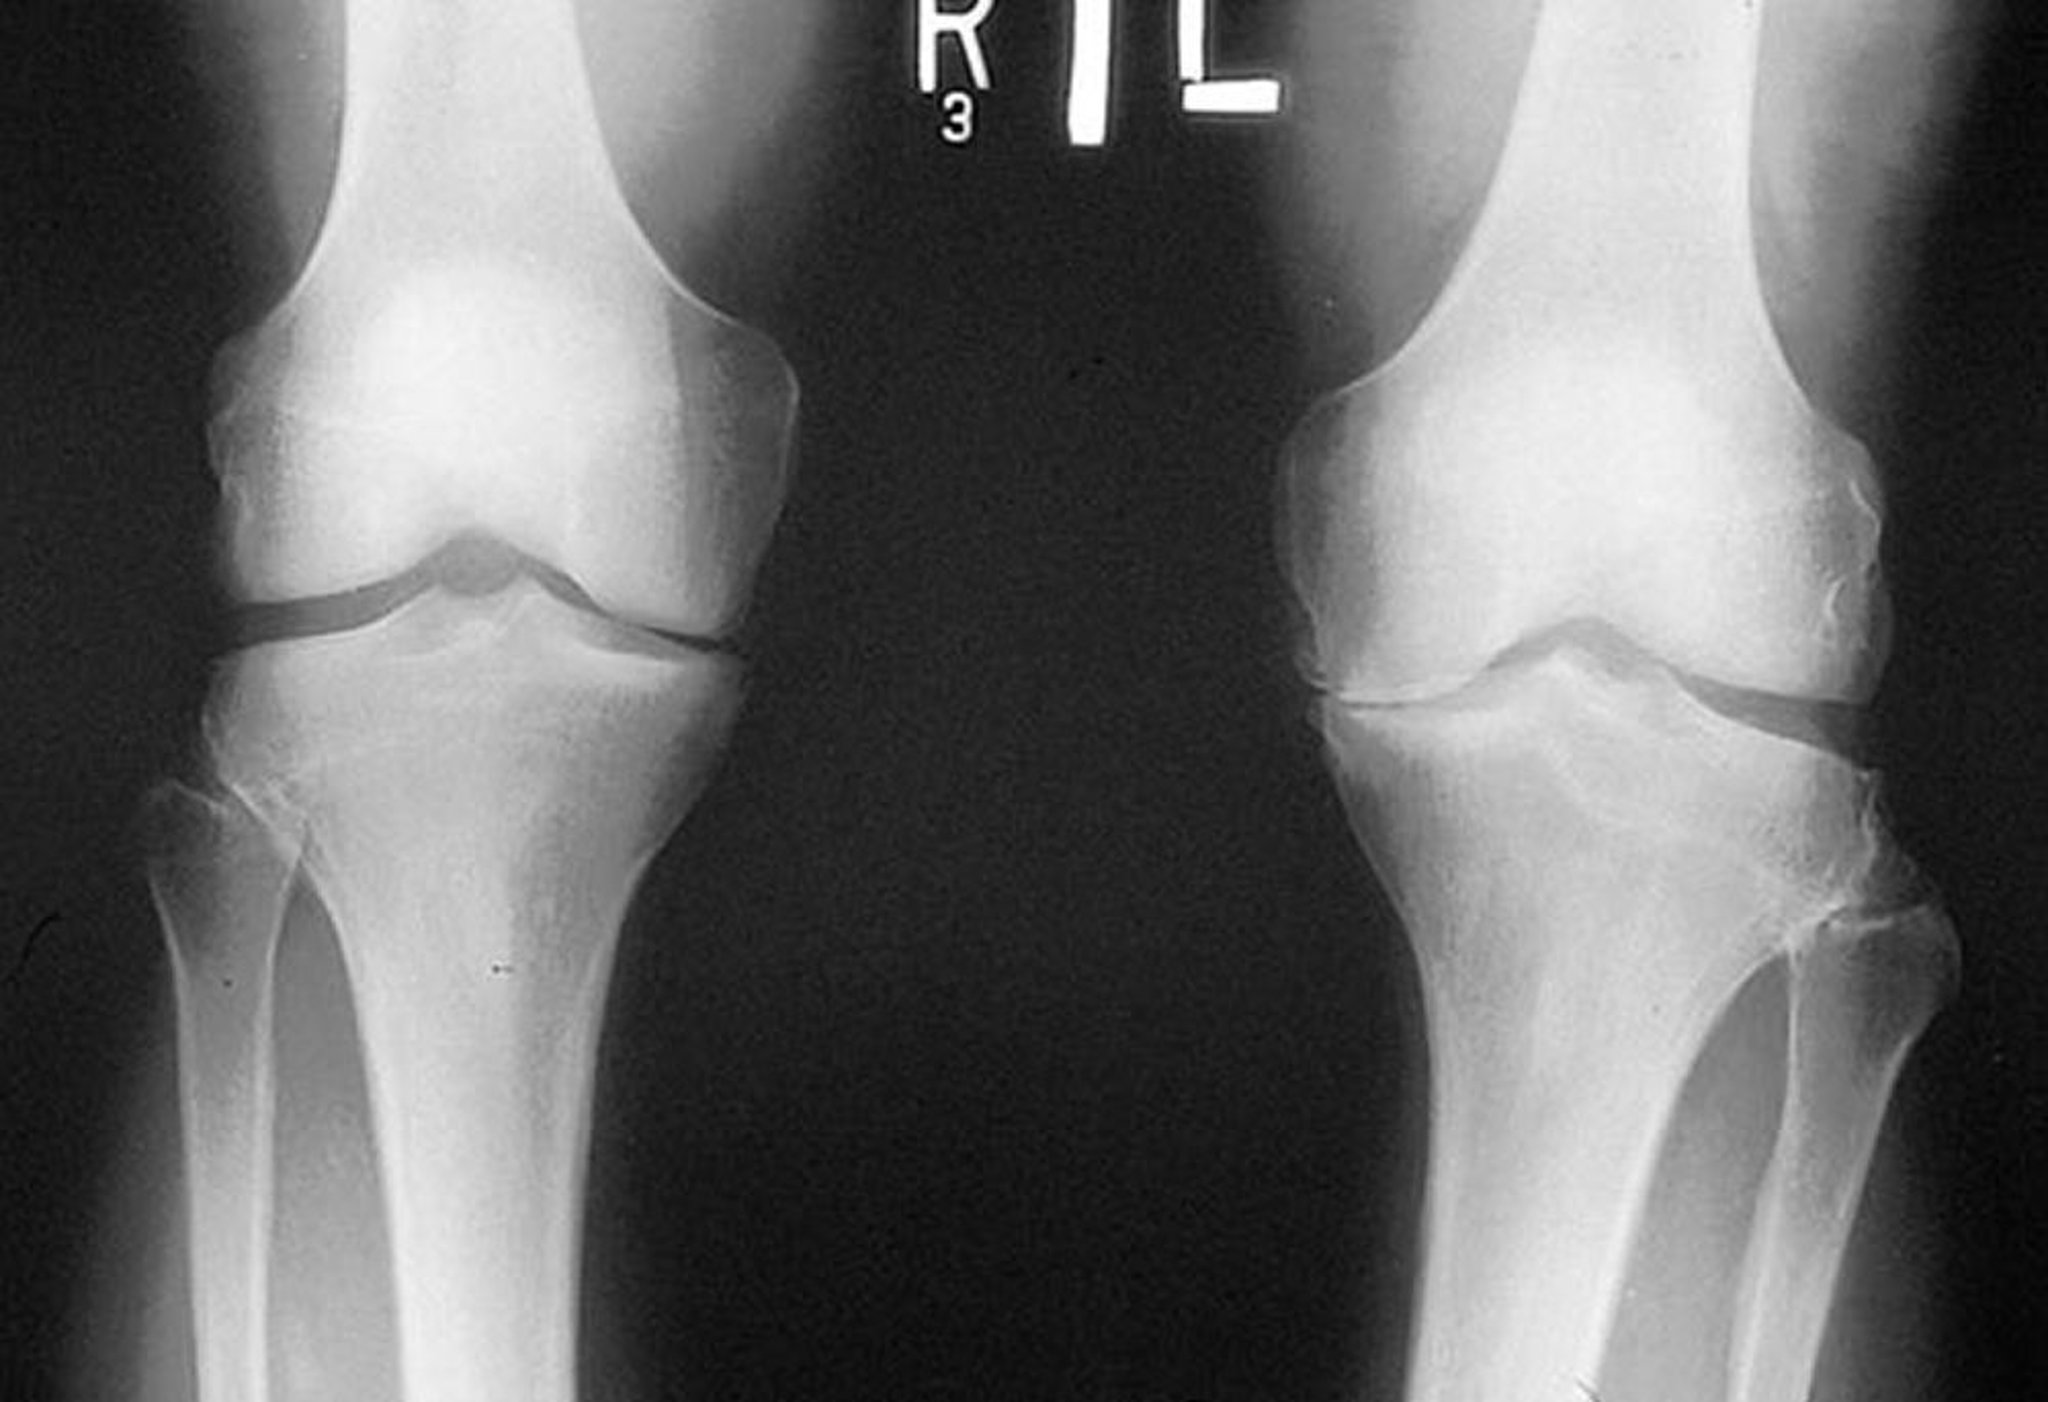

Röntgenaufnahme des Knies bei Arthrose

Diese Röntgenaufnahme, die im Stehen gemacht wurde, zeigt, dass der tibiofemorale Gelenkspalt im medialen Kompartiment beider Knie eng ist, besonders links. Marginale Osteophyten sind sichtbar. Es besteht ein Abrieb des linken Tibiaplateaus.

By permission of the publisher. From Myers S: Atlas of Rheumatology. Edited by G Hunder. Philadelphia, Current Medicine, 2005.